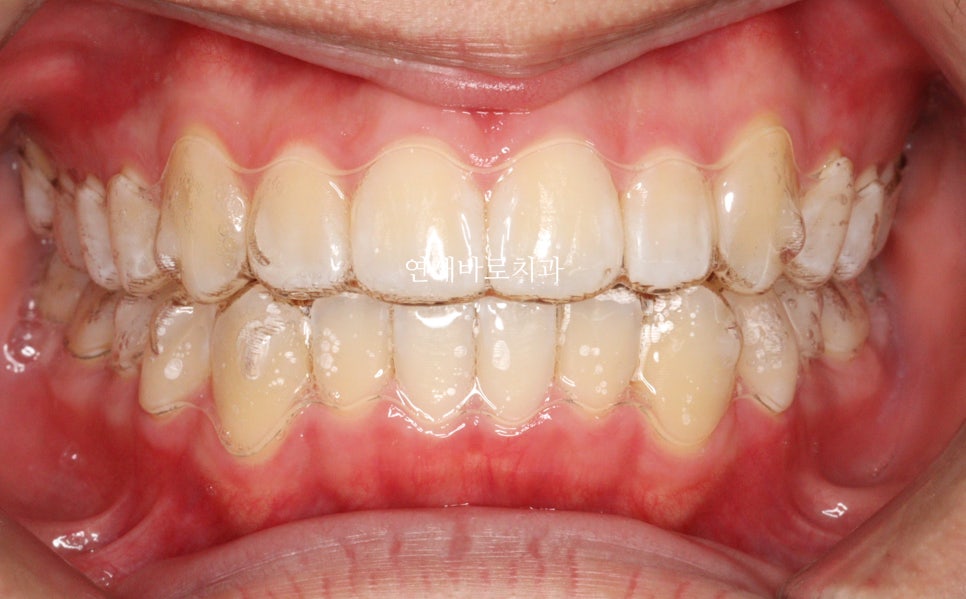

환자분과 비슷한 환자분의 치료 전 후를 볼 수 있으면 환자분도 이해가 잘 될겁니다.

그리고 신뢰도도 향상되어 앞으로의 교정치료를 받는 기간동안 원장님과 병원을 신뢰하며 다닐 수 있게 될겁니다.

비슷한 환자를 보여달라고 요청해보시는 것은 굉장히 날카로운 질문입니다.

충분한 임상경험이 있는 원장님들은 비슷한 경우를 보여주실 겁니다.

이때 바로바로 보여주시는 분이 계시다면 믿고 치료를 진행해도 좋습니다.